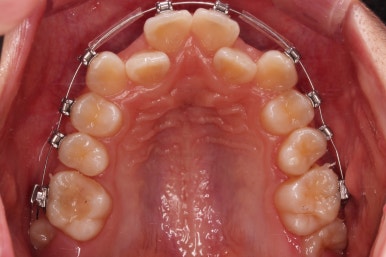

연산동치과 초진 시, 입안의 모습입니다.

보시다시피 앞니쪽이 많이 삐뚤고요. 어금니쪽이 긴밀하지 못한 부정교합이 있네요.